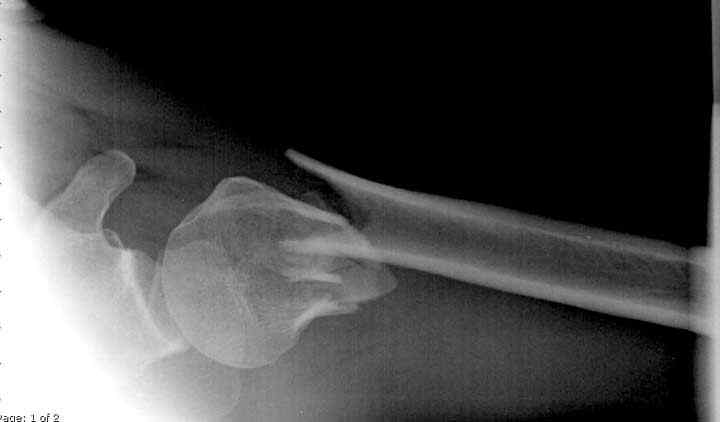

Здесь пример открытой репозиции 57 летнего с переломом плеча (1,2) смещение обнаружено на интероперационном снимке. При нормальной прямой проекция (3) угловое смещение обнаружили в аксиальной проекции (4)